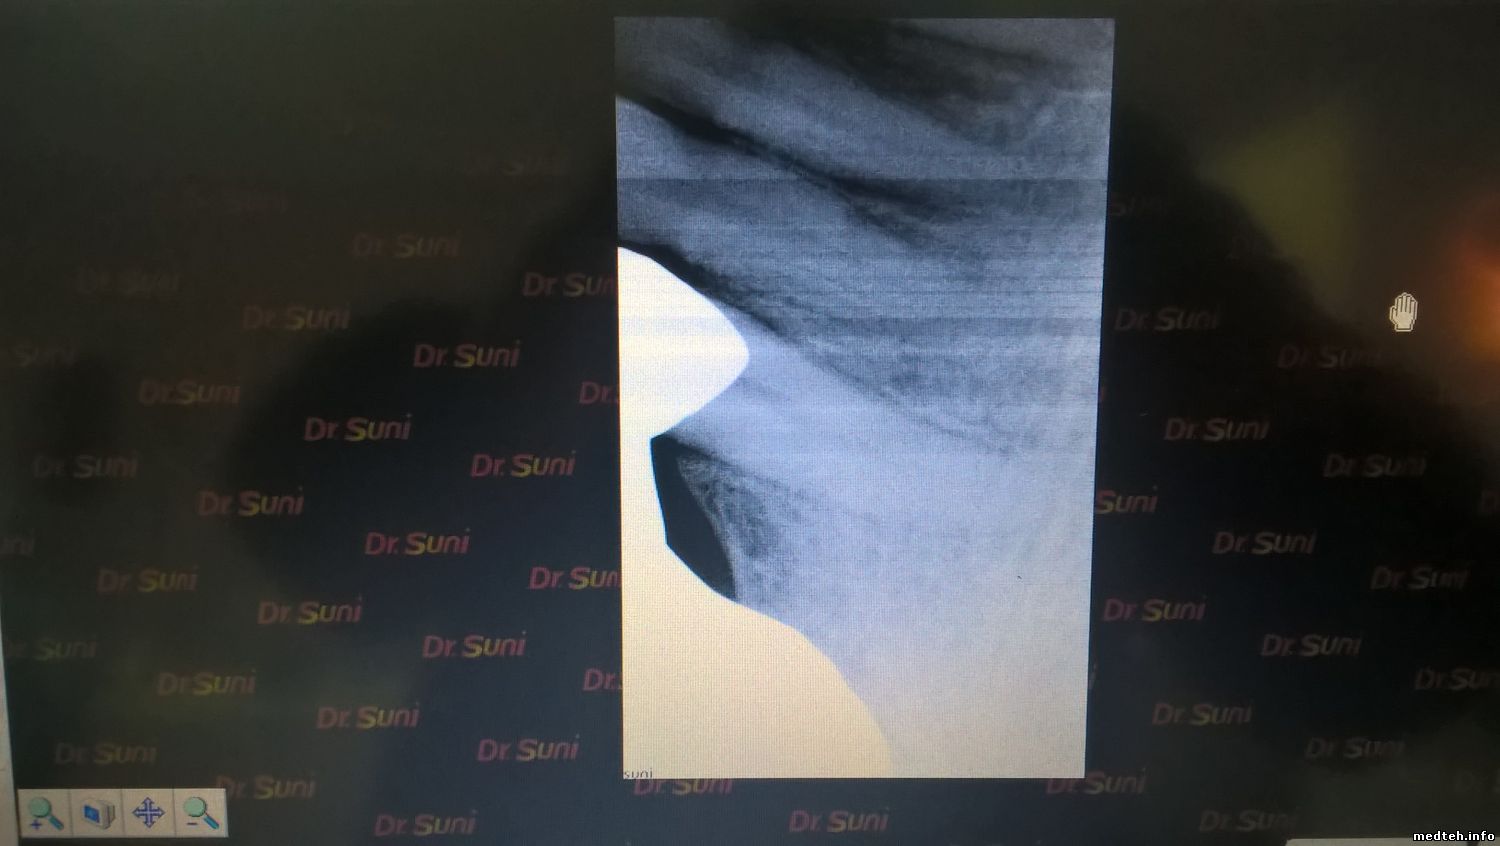

Визиограф Др. СУНИ выкидывает номера иногда сам по себе может сделать пустой снимок без воздействия рентгена на снимке какие то полосы.

Также могут иногда вдруг появиться полосы на снимках сделанные под воздействием рентгена .

4331447.jpg (87.8 Kb) · 7431121.jpg (97.7 Kb)